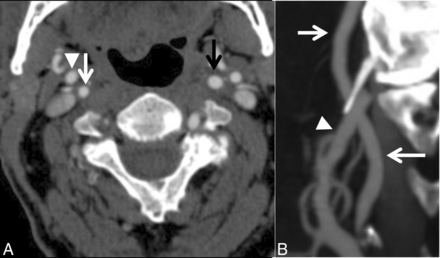

A case with near-occlusion without full collapse. A, Axial CTA at the level of the distal extracranial ICA. B, Sagittal reformat of A. The distal right ICA (white arrow) is narrower than the contralateral ICA (black arrow) and similar to the right ECA (arrowhead) but otherwise is normal-appearing (not threadlike).